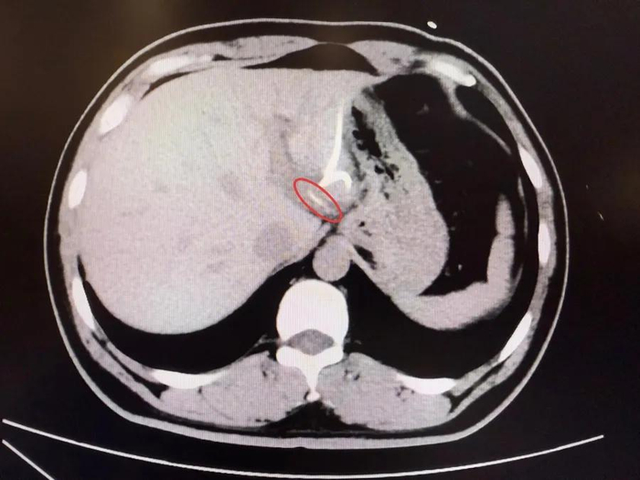

Mãi đến khi chụp CT, các bác sĩ mới phát hiện một vật thể dài, nhọn trong gan trái, gần vùng nối với dạ dày, hình dạng giống hệt… một chiếc xương cá! Hóa ra, chiếc xương này đã xuyên qua thành dạ dày, “chui” thẳng vào gan, gây nhiễm trùng và tạo ổ mủ lớn.

Sau hơn 3 tiếng đồng hồ, các bác sĩ đã tìm thấy chiếc xương cá dài 3,5cm, sắc nhọn như kim, cắm sâu trong gan trái. Sau ca mổ, anh Lý hồi phục tốt, nhiệt độ cơ thể trở lại bình thường, ổ áp xe dần tiêu biến và quan trọng hơn cả, anh giữ được nguyên vẹn lá gan của mình.